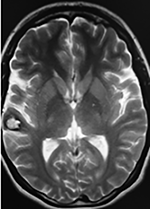

El estudio de control de RMN se observa la brecha quirúrgica y ausencia de lesión (figs. 1, 2 y 3).

Figura 2:

Cortes axiales en ponderación T1, cambios postquirúrgicos.